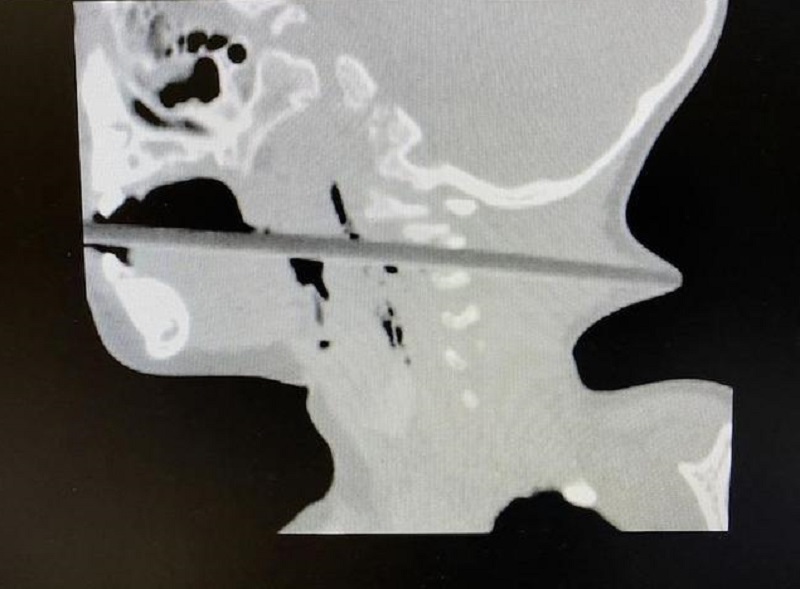

醫院神經外科主治醫生邱德智立即為林林安排全面的CT檢查。結果顯示,二十多厘米的筷子從傷者的口腔進入,經過咽部後壁,通過頸椎2、3間隙,一直向後到達後頸,幾乎戳穿了皮膚,從後頸可以清晰地看見筷頭。雖然筷子沒有傷到患兒的食道和氣管,但可能損傷椎動脈和頸神經,手術中很有可能造成大出血危及生命。